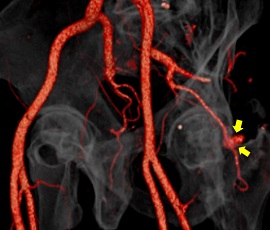

[血管系IVR] 動脈瘤 経動脈的コイル塞栓術

CTA画像

コイル挿入後